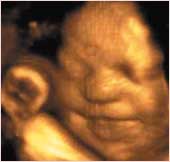

Babex عبارة عن إضافة إلى برنامج اكسل «Excel AddIn» سوف تساعد الإمهات على مراقبة مراحل تطور ونمو أجساد أطفالهن (طول الطفل، وزنه، محيط رأسه...، إلخ ). وكل نقطة جديدة تسجل سوف تقارن بالقيمة ........التفاصيل